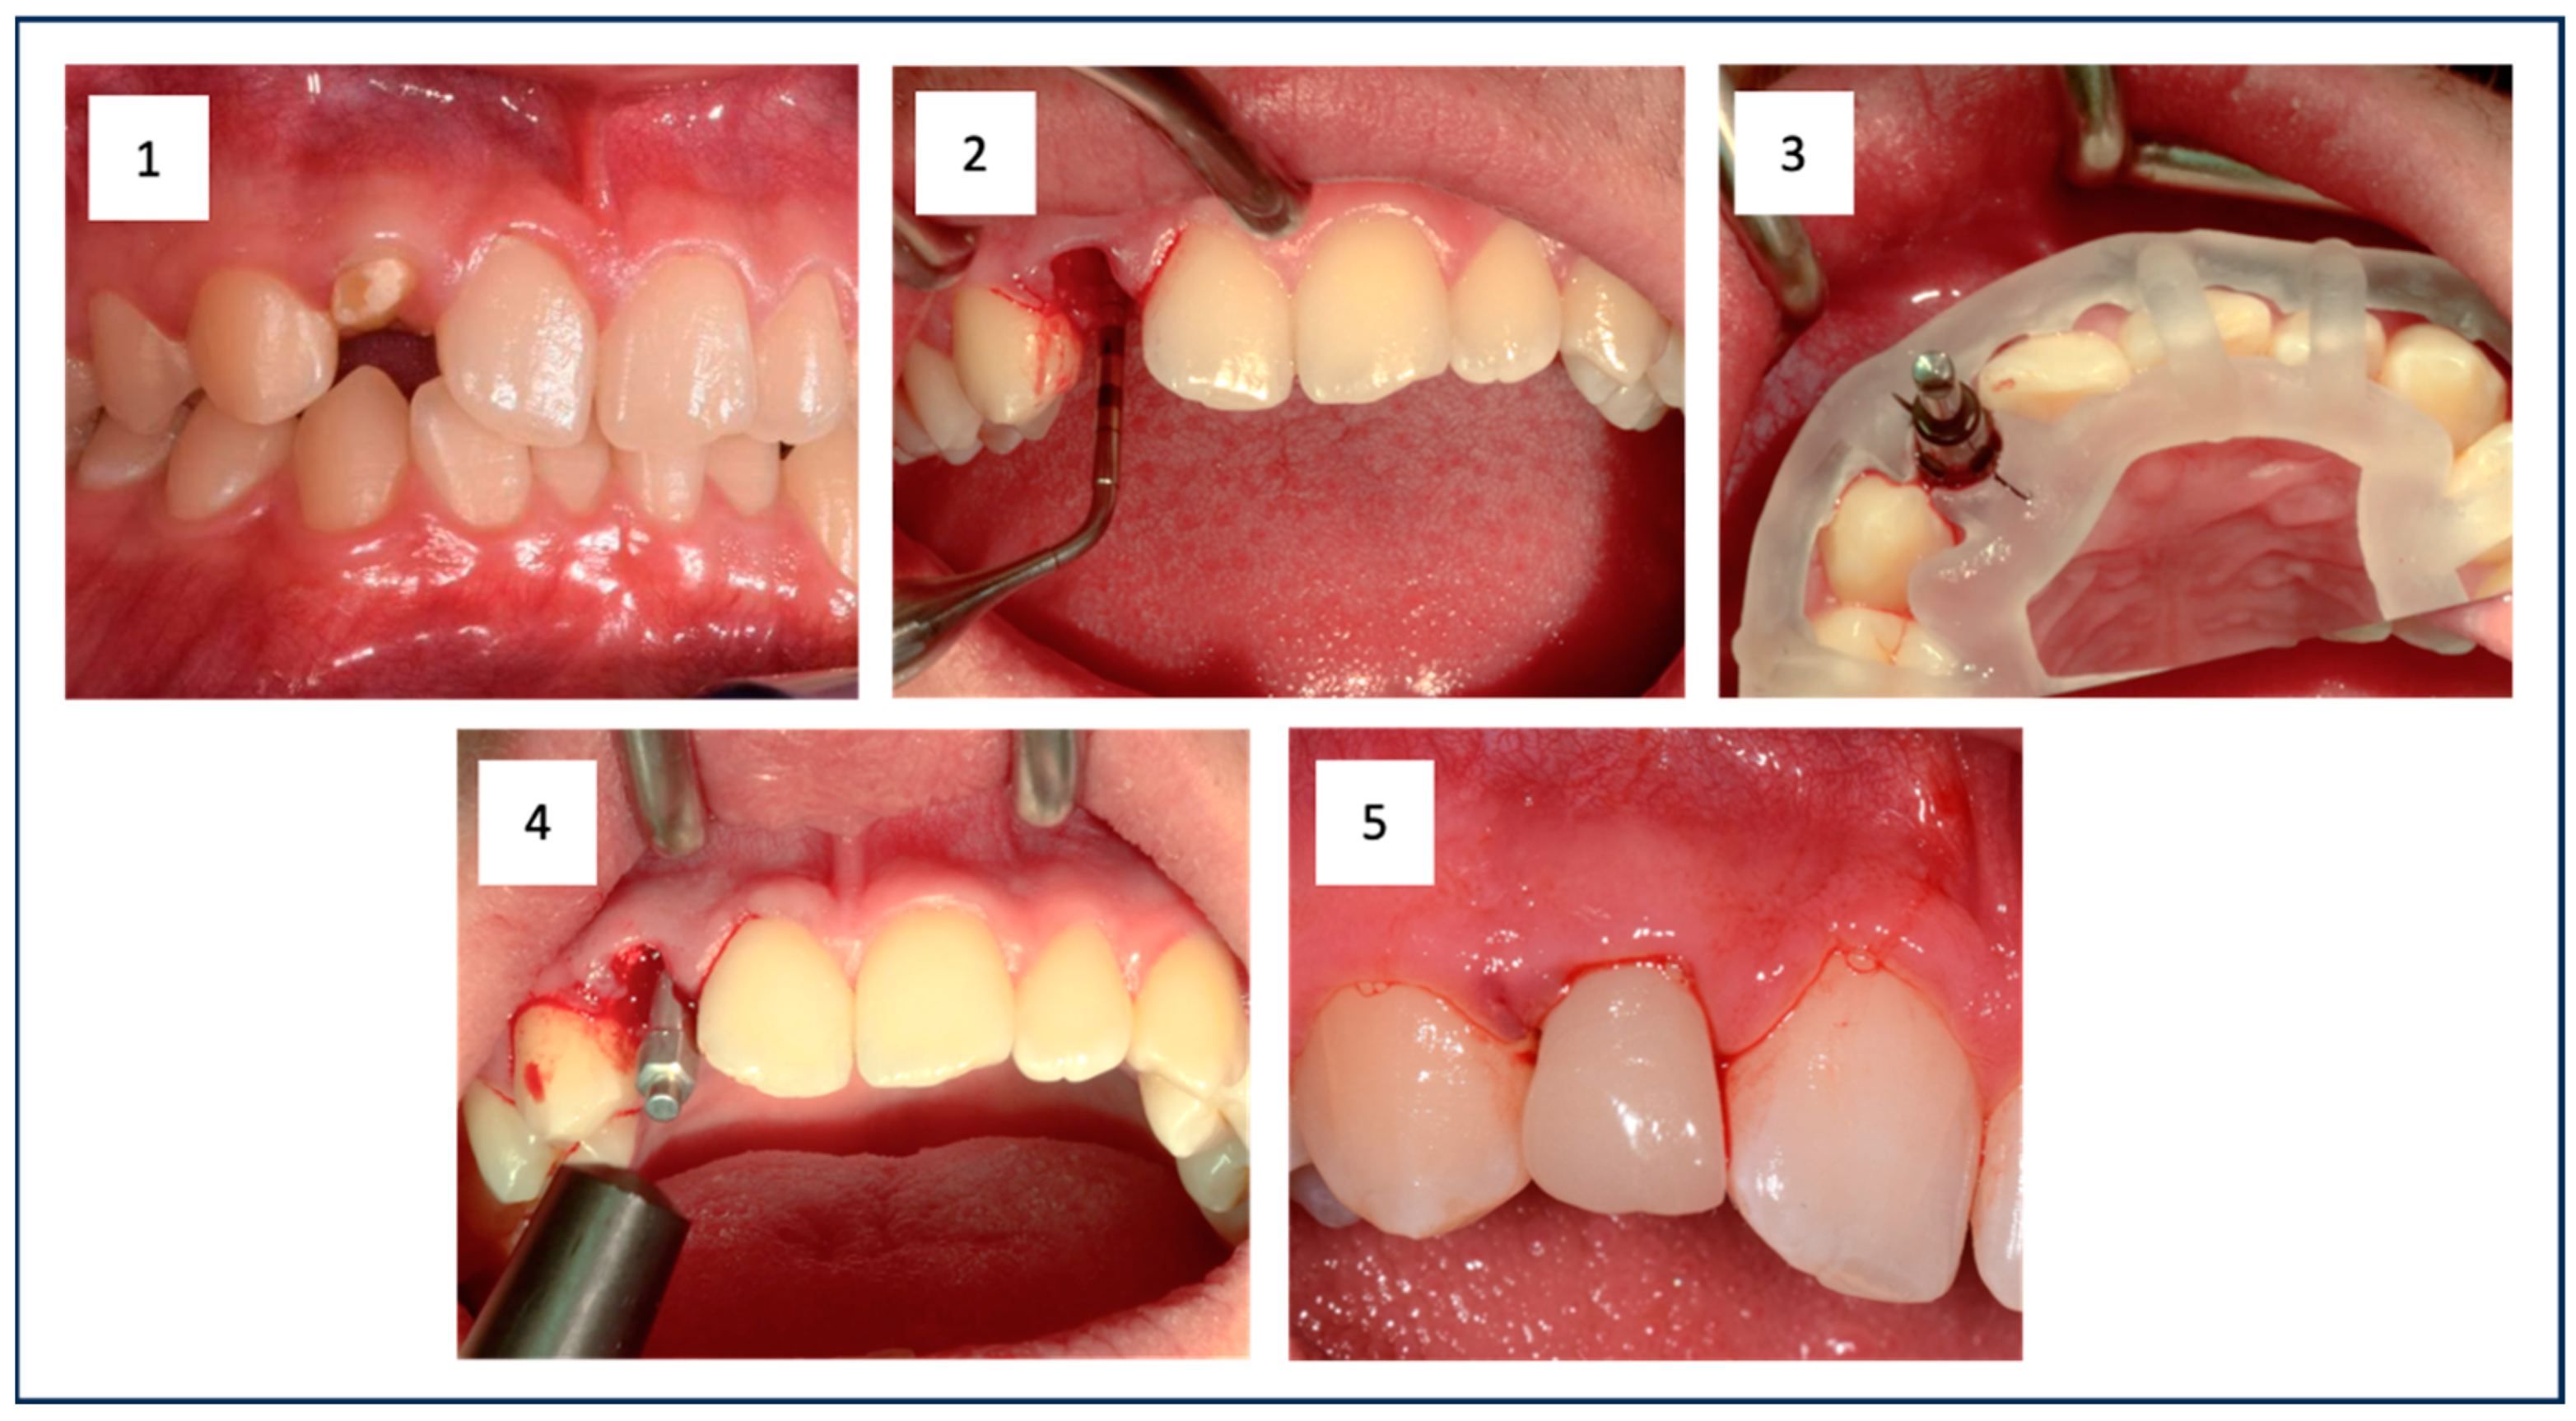

At the beginning of the implant surgery, the patients received local anesthesia, and if possible, the fit of the surgical guide was checked in the patient’s mouth. For patients in Group 1, atraumatic extraction of the tooth was performed, followed by careful curettage of the extraction socket (Figure 1(1,2)). For the patients in Group 2, a full mucosal-periosteal flap was raised, and the bone was exposed.

In both groups, the implant bed preparation was carried out using the SIC-Guided Surgery Kit (SIC Invent©, Basel, Switzerland). The preparation followed the manufacturer’s instructions and was based on the implant type, performed fully guided using the prepared surgical guide and cooled with sodium chloride solution (0.9%) (Figure 1(3)). A tapered implant with a conical internal connection (SIC vantage tapered, SIC Invent©, Basel, Switzerland) was then inserted. For the preparation and implant insertion, the Implantmed Plus SI-1023 drive unit with automatic torque control (W&H©, Bad Reichenhall, Germany) was used. This allowed the measurement of the insertion torque (IT) of the implant during insertion. Additionally, the ISQ value was measured with resonance frequency analysis (RFA) (Osstell® IDX, Osstell AB, Gothenburg, Sweden) (Figure 1(4)). Cut-off values for the primary stability of the implant were set at an IT of ≥25 Ncm and an ISQ of ≥60. Adhering to or exceeding these values was essential to ensure sufficient primary stability for secure osseointegration in immediate restoration. Before the provisional restoration could be placed (Figure 1(5)), the jumping distance between the implant and the buccal bone lamella was filled with bone substitute (Cerabone®, Botiss Biomaterials, Zossen, Germany) for the patients in Group 1. For patients in Group 2, this step was not necessary.

Figure 1. The initial situation shows the root remnant of the upper right lateral incisor (1). The empty extraction socket is visible after minimally invasive tooth removal (2). The situation after guided implant placement is shown, clearly illustrating the surgical guide and the properly oriented implant (3). This was followed by RFA measurement to document sufficient primary stability in addition to measuring the insertion torque (IT) (4). Finally, the prefabricated provisional restoration was fixed (5).